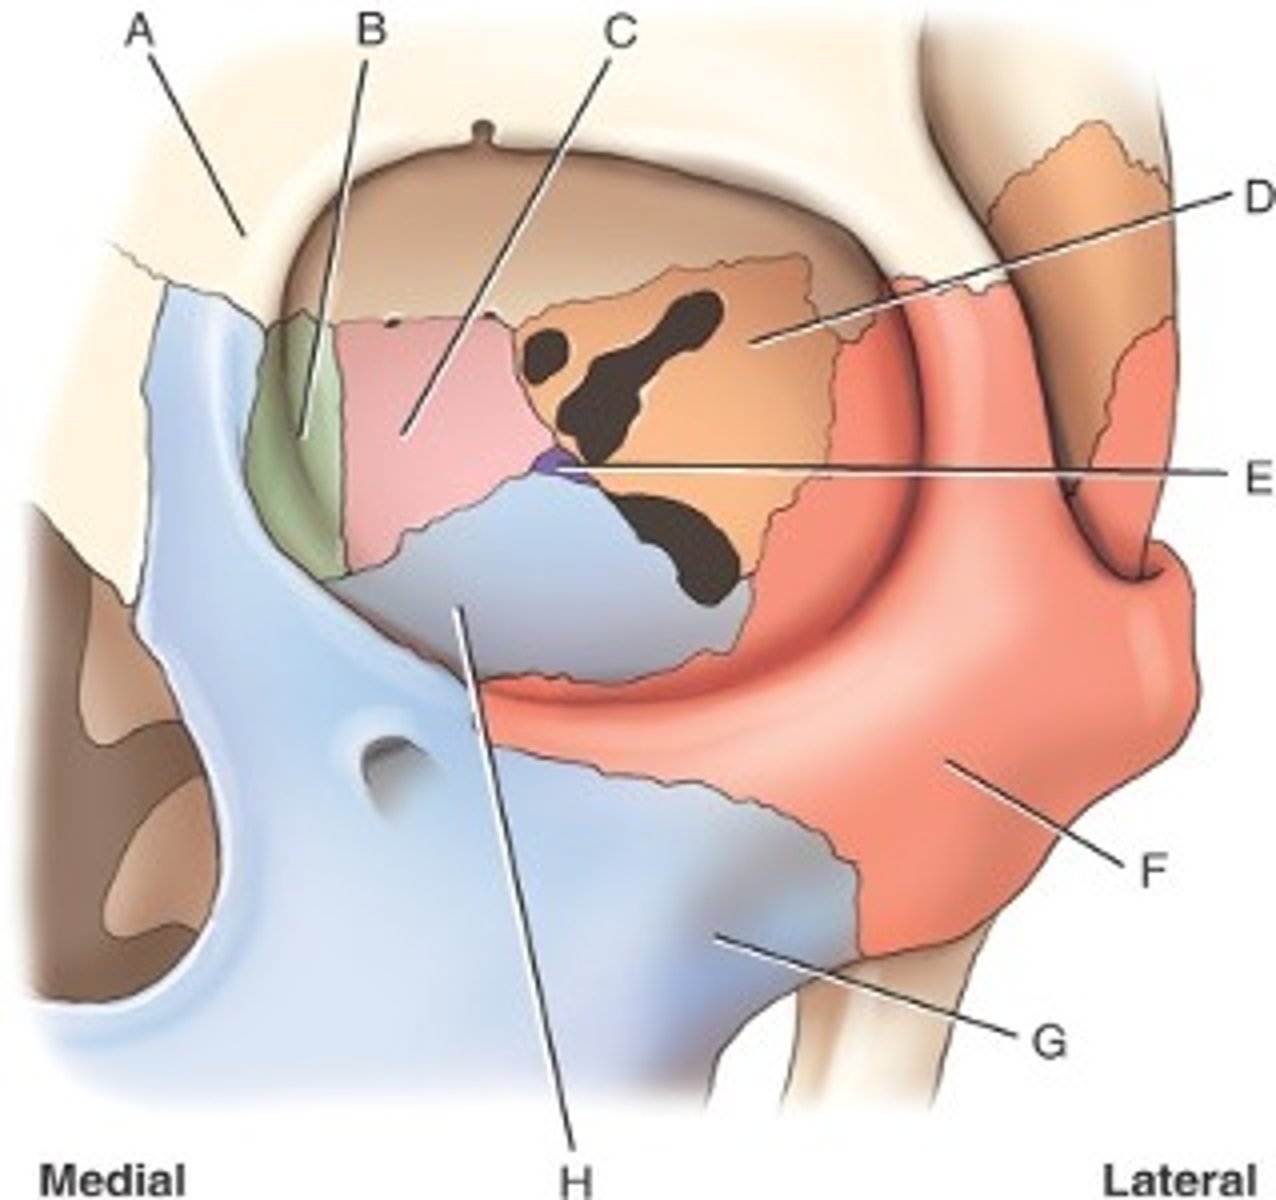

What is B

frontal bone

What is A

ethmoid

What is C

sphenoid

what is D

Palatine

What is E

Zygoma

What is F

Maxilla

What is G and H

optic foramen in orbit

sphenoid strut